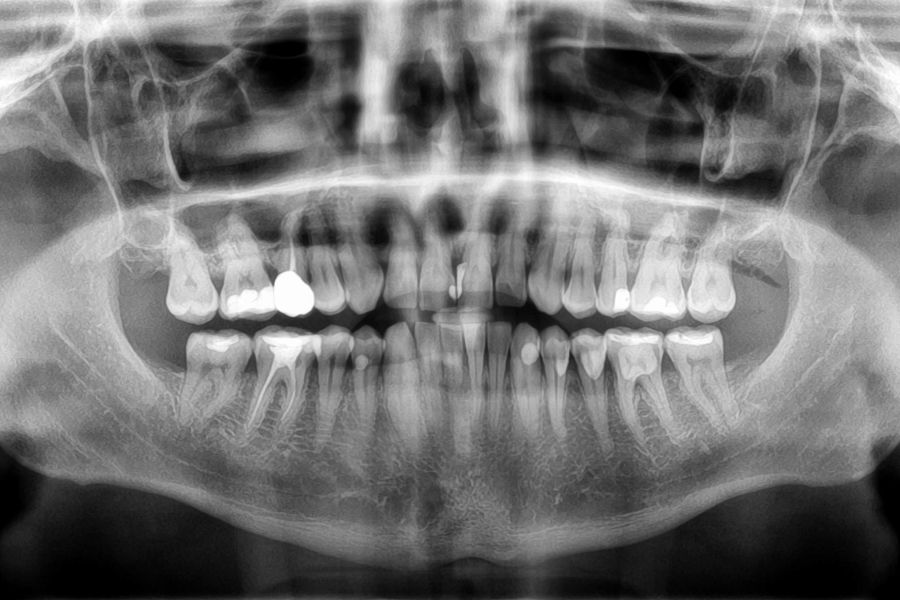

Grâce à des outils numériques avancés, une radiologie intégrée, un suivi photographique rigoureux et un laboratoire en interne, nous optimisons chaque étape de votre prise en charge pour allier efficacité, confort et sécurité.